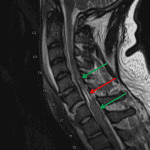

- Severe (nearly 2 cm) anterolisthesis of C6 on C7 with bilateral jumped C6-C7 facet joints

- Widening of the epidural space ventrally at C5-C6 consistent with a small epidural hematoma

- Extensive prevertebral edema

Severe traumatic malalignment at C5-C6 with x mm anterolisthesis and bilateral jumped facets. This malalignment in combination with a thin ventral epidural hematoma results in severe spinal canal compromise concerning for severe cord injury or transection. Noncontrast cervical spine MRI could further assess the degree of ligamentous injury and assess the cord.